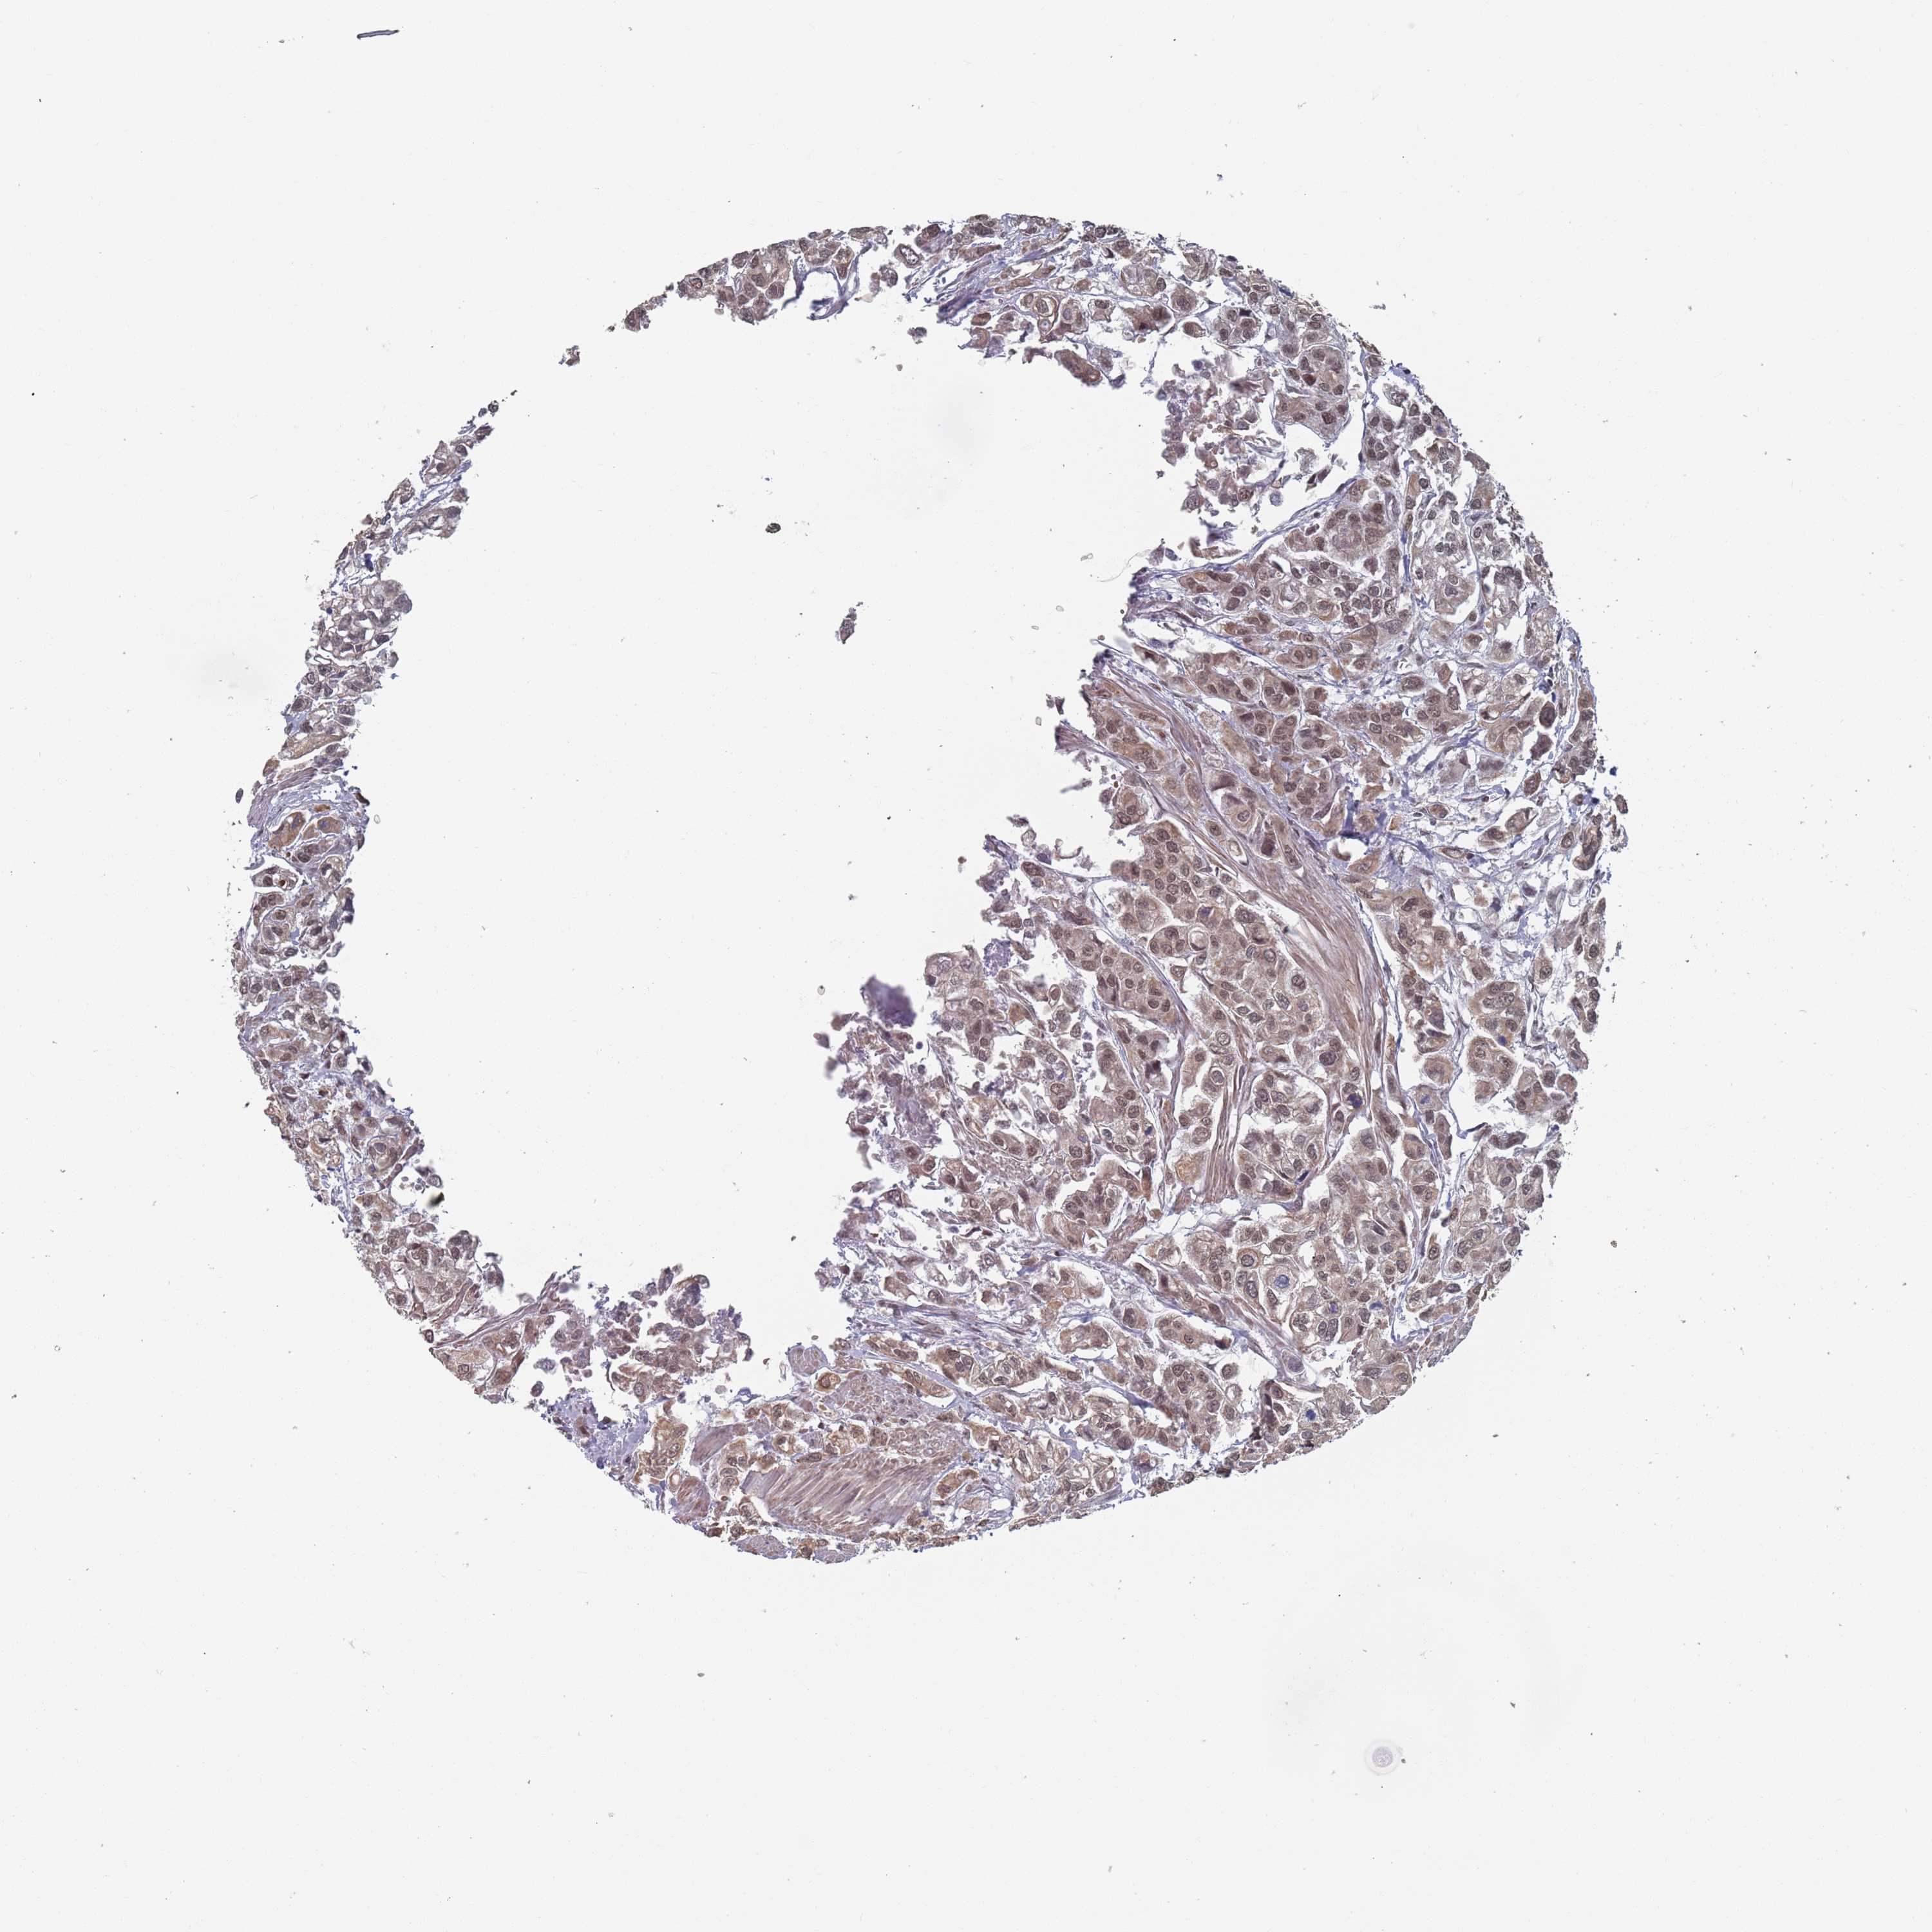

UROTHELIAL CANCER - Protein expressioni

A mouse-over function shows sample information and annotation data. Click on an image to view it in a full screen mode. Samples can be filtered based on level of antibody staining by selecting one or several of the following categories: high, medium, low and not detected. The assay and annotation is described here.

Note that samples used for immunohistochemistry by the Human Protein Atlas do not correspond to samples in the TCGA dataset.

Antibody stainingi

Antibody staining in the annotated cell types in the current human tissue is reported as not detected, low, medium, or high, based on conventional immunohistochemistry profiling in selected tissues. This score is based on the combination of the staining intensity and fraction of stained cells.

Each image is clickable and will lead to virtual microscopy that enables deeper exploration of all samples and also displays staining intensity scores, fraction scores and subcellular localization as well as patient and tissue information for each sample.

Antibody HPA049101

Staining

High

Medium

Low

Not detected

Intensity

Strong

Moderate

Weak

Negative

Quantity

>75%

75%-25%

<25%

None

Location

Nuclear

Cytoplasmic/membranous

Cytoplasmic/membranous,nuclear

Urothelial carcinoma, High grade

Urothelial carcinoma, Low grade